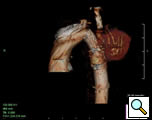

Because of the patient’s prior coarctation repairs and the morphology of the pseudoaneurysm, an endovascular repair was felt to be desirable. Based on preoperative measurements of the CT angiogram, a tapered endoprosthesis 9.5cm in length with 16mm proximal diameter and 20mm distal diameter (W.L. Gore & Associates, Inc.), originally marketed as an iliac limb, was selected for use. The patient was taken to the operating room. After induction of general anesthesia, percutaneous right femoral artery access was obtained and a measuring pigtail catheter was advanced into the distal aortic arch. An aortogram was performed which demonstrated the aortic arch and pseudoaneurysm morphology (Figure 3).